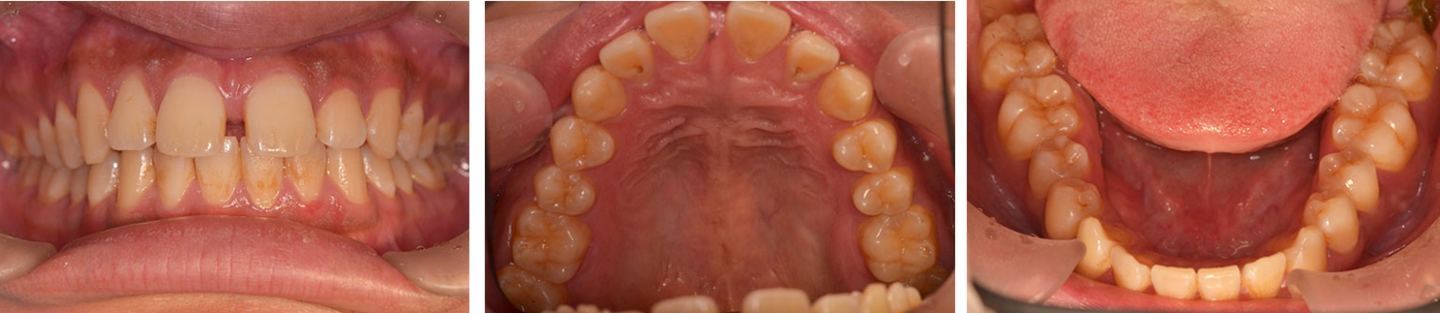

17歳男性 歯列不正 上下抜歯

治療前の写真

治療前

治療後の写真

治療後